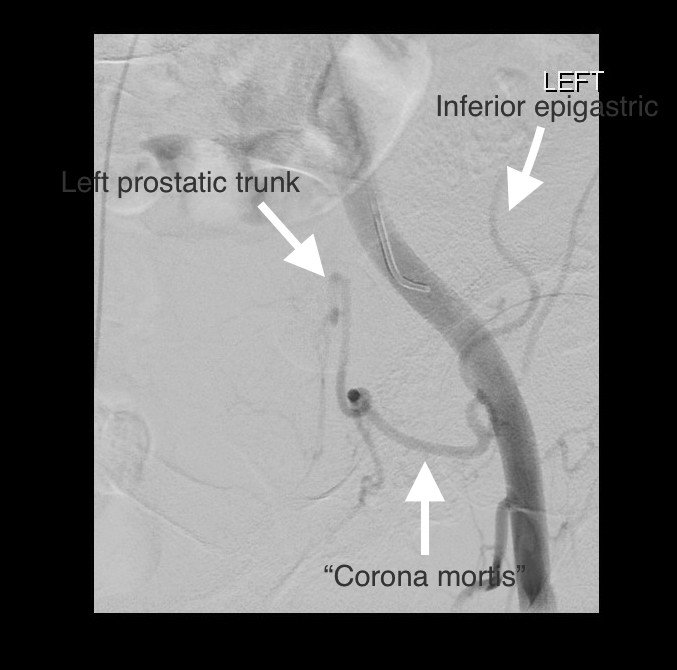

Ani Mirakhur On Twitter Prostate Artery Embolization Via Corona Mortis Aberrant Obturator On The Left Bph Notjusttrauma Withoutascalpel Miips Sirrfs Https T Co Ewtlpdvjmz

The Image Is Of The Digital Substraction Angiography Of The Left Lower Download Scientific Diagram

John Demeritt On Twitter Rare Prostate Artery Origin From Corona Mortis Identified On Preprocedural Cta Value Of Planning Cta In Pae Sirrfs Pae Foamed Foamrad Miips Https T Co 291sjmfqp4